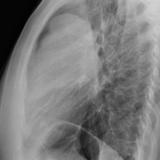

Case 8b Thymoma Lat

Date: 03/27/2009

Views: 14091